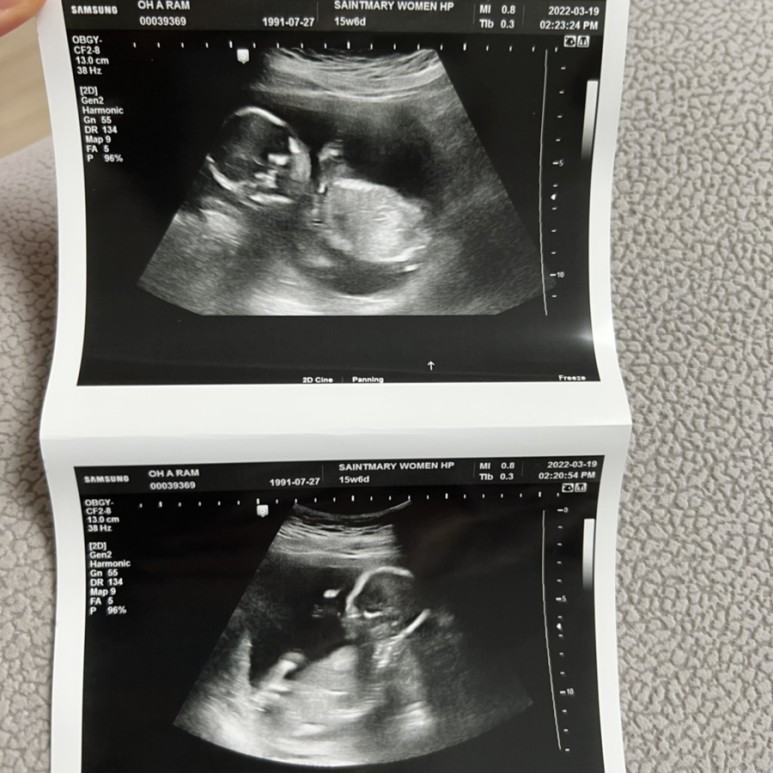

15주기형 아동검사 2차 받은 기형아 검사 2차는 피를 뽑고 초음파 쉽게 보는데 기형아 검사 2차 하면서 우리는 취약x증후군 검사도 같이 했다.

검사 후 2주 후 문자로 연락이 오는 호랑이는 2차 기형아 검사, 취약x증후군 선별검사 모두 통과!

이젠 꽤 인간스러워져서 신기했어.15주 6일 병원에 가서 성별도 같이 보려고 했지만 호람이는 절대 보여주지 않았다.